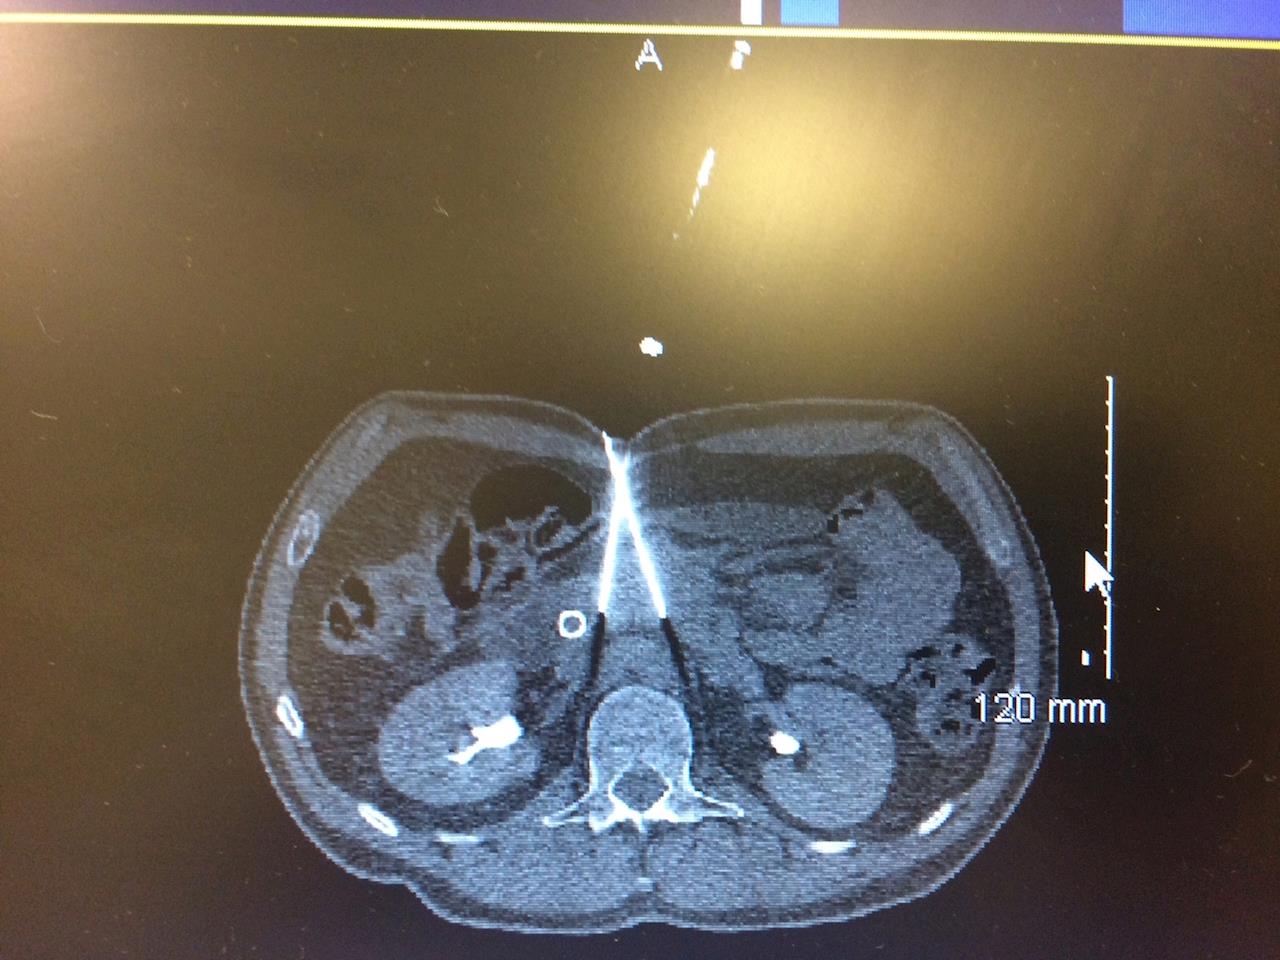

Hi everyone! We flew to London on Sunday 19 June for Cory's treatment by Professor Edward Leen. Cory checked in to The Princess Grace Hospital on Wednesday 22 June for his first treatment, which was RFA (Radio Frequency Ablation) to his liver tumour. We met Professor Leen who explained the procedure and met the wonderful anaesthetist Dr John Picard who filled us with confidence. The procedure involved a CT guided needle that delivered heat to destroy the tumour. Cory was in alot of pain afterwards which was managed and he was discharged as scheduled the following day nursing a couple of tiny puncture marks and feeling very tender. The week was spent recuperating in preparation for the Nanoknife procedure on Tuesday 28 June. During the set up for the Nanoknife on the pancreatic tumour, CT images were taken of the liver and it showed that tumour had turned black and that tumour was dying. Professor Leen saw a tiny tumour adjacent to the ablated tumour which he treated with the Nanoknife along with the primary pancreatic tumour. He also observed a cyst on the pancreas that was aspirated and tested negative for malignancy. Cory had ALOT of nerve pain after the procedure which is gradually subsiding. Once again, little puncture marks and discharged the following day. We now continue with chemo and have to patiently wait for the next CT scan which was recommended at 3 months post procedure. We flew back to the Gold Coast and went directly to the hospital for an oncology appointment. Cory was treated like a rock star! Everyone is so fascinated and full of admiration at Cory, he is an inspiration. The following morning we were back at hospital for a portacath to be inserted into Cory's chest and then straight onto chemo. 3 surgical procedures in 3 weeks...wow. After a day of rest Cory decided that he wanted to show his support to everyone involved in the Garage Sale fundraiser - BIG SHOUT OUT to Mel, Shane, Glen, Lena, Damo, all the incredible baking ladies, Peter, Jenny, Vicki, Ruth, Bridie, Terry's Panel Shop (if I have missed any names please accept my apology, but you know who you are and we love you) and the Quiz night organised by Port Taranaki. Cannot express how humbling and honoured Cory felt to know that he is loved and thought of. While we only managed brief visits at both events it did wonders for Cory's spirits. So now my job is to feed Cory clean, healthy food, keep his spirit strong and work to secure ongoing treatment in New Zealand. Cory and I are determined to help other people with pancreatic cancer by sharing Cory's remarkable story and how he is overcoming the statistics every single day. I have attached an image of the Nanoknife scan, the needles deliver electricity to the tumour. There are some interesting videos on youtube detailing the procedure for anyone interested. Once again, thank you for the continued support, we have a long way to go, thank for coming on this journey with us. Love Cory and Sherrie xxx